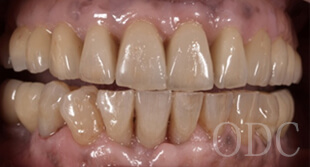

⑤ 美しい最終補綴

専属の歯科技工士により、芸術まで高められた最終補綴物を貴方に、心を込めて贈ります。これらのテクニックはほんの一部です。オールオン4は高度なインプラント技術を必要とする治療の1つです。後悔しない為にクリニック選びは慎重に行って下さい。

インプラント治療で、もっとも高い技術力が必要とされるうちの1つが全顎的な症例です。噛み合わせを熟知していなければ顎関節に支障をきたし補綴物の永続性は保てないのです。そしてオーキッド歯科クリニックのインプラント治療を支えるデンタルテクニシャン(歯科技工士)の技術も重要です。

初診時87歳、男性。上顎は歯周病により残存歯を長期的に機能させることが困難と判断し、全て抜歯。出来る限り早期の咬合機能の回復と審美性の実現が求められ、上顎は「4本のインプラントで失った全ての歯を固定し、手術当日から噛む機能を回復させることが可能」なオールオン4という術式を選択。オールオン4は「治療期間」「経済性」「審美性」「外科的侵襲」などのあらゆる負担を軽減した全く新しいコンセプトの画期的なインプラント治療です。 下顎の欠損部位に対しても、術前の診査診断をしっかり行い合計5本のインプラントを埋入しました。

インプラント治療を成功に導く為に必要不可欠な歯科技工。インプラント補綴は、特に技工士の技術が重要となる。オールオン4において、“口の中の見える部分”は全て歯科技工士の仕事なのです。当医院のオールオン4補綴はインプラント補綴で有名なノーベルバイオケア社公認インストラクター 志田和浩氏によるものです。本症例は、1歯1歯プロセラを装着した、オールオン4の上部構造としては最高級のものの一つです。